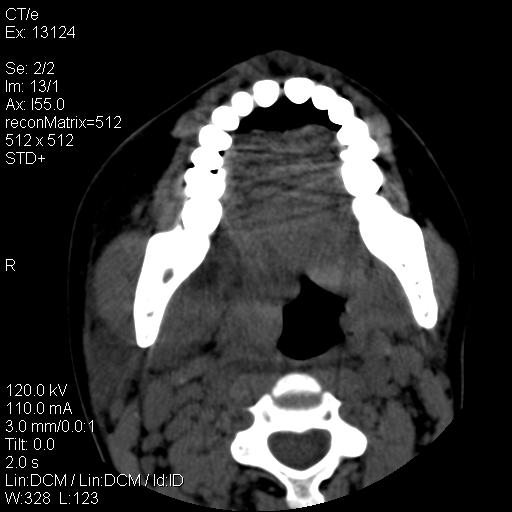

标题: CT18257:女,29岁,右下磨牙痛 [打印本页]

标题: CT18257:女,29岁,右下磨牙痛

女,29岁,右下磨牙痛,因产后2月,故未治疗。现右颌肿痛伴张口困难。请大家看看右侧鼻咽部、口咽部是否

1.考虑右侧下颌区脓肿(牙源性)

考虑右侧下颌区脓肿(牙源性)!支持!

考虑右下智齿冠周炎伴周围软组织炎症,脓肿形成

1)考虑右侧下颌区软组织脓肿(牙源性)。2)鼻咽部炎性改变;建议追踪复查。3)右侧上颌窦炎。4)双侧下鼻甲黏膜肥厚。

考虑右侧下颌区脓肿。

右下颌软组织脓肿

1)考虑右侧下颌区牙源性软组织脓肿。2)右侧上颌窦炎。3)双侧下鼻甲黏膜肥厚。4)鼻咽部炎性改变;建议追踪复查。

考虑右下智齿冠周炎伴周围软组织脓肿形成。